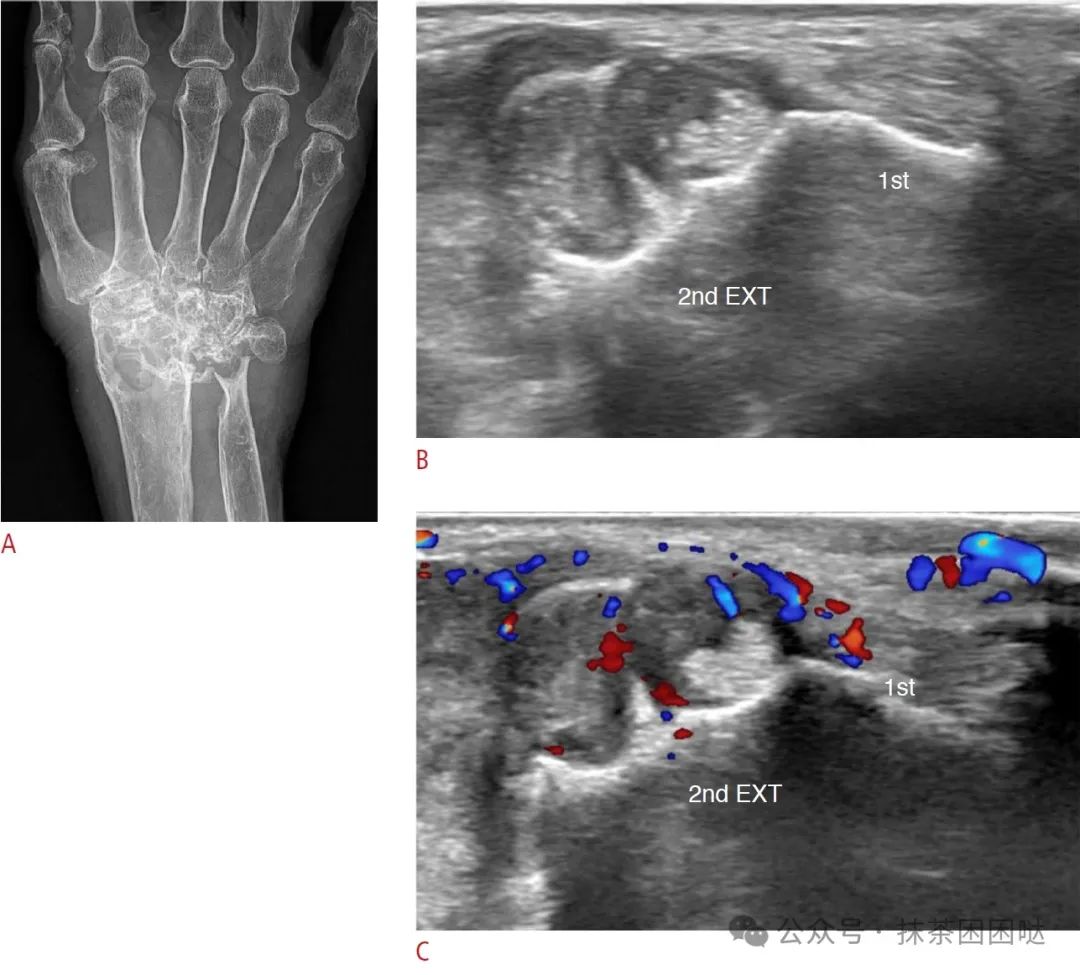

一名 75 岁女性腕部慢性伸肌腱鞘炎 A. X线平片显示严重的关节周围骨侵蚀,伴有腕关节畸形。B. 同日超声检查显示第一和第二伸肌(EXT)间隙腱鞘弥漫性增厚,邻近骨质侵蚀。C. 彩色多普勒超声检查显示病变血管分布明显增加。